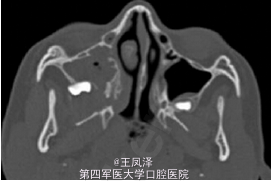

罕见上颌骨中央性肌纤维瘤一例

患者女,9 岁,发现右侧上颌骨无痛性肿块 3 个月余。